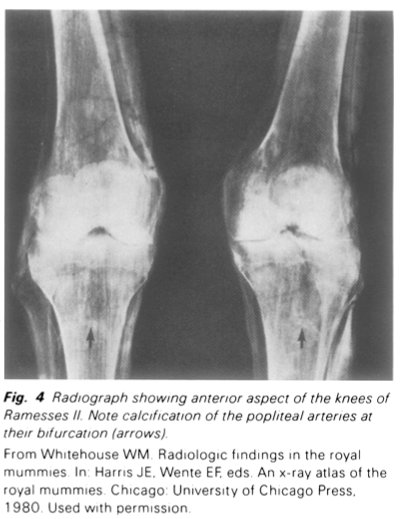

Extensive histologic analysis of mummies began, however; well before the development of the scanning electron microscope. In 1912, Shattock' made sections of the calcified aorta of Pharaoh Merneptah; and the work of Sir Marc Armand Rufer, published posthumously in 1921, is our most valuable early source of information about vascular disease in ancient Egyptians. Ruffer was able to study a relatively large number of tissue specimens from mummies, mainly from New Kingdom (1600-1100 BC) burials, but covering a wide period of time. In a mummy of the 28th to 30th Dynasty (404-343 BC), he observed atheromas in the common carotids and calcific atheromas in the left subclavian, common iliac, and more peripheral arteries. Ruffer concluded from the state of the costal cartilage that this mummy was not that of an old person. A mummy of a man of the Greek period (ca. 300 to 30 BC), who died at not over 50 years of age, showed atheromas of the aorta and brachial arteries. Since the discoveries of Rufer, numerous other mummies, whose ages at death ranged from the 4th to the 8th decade, have shown similar vascular changes (Fig.4).